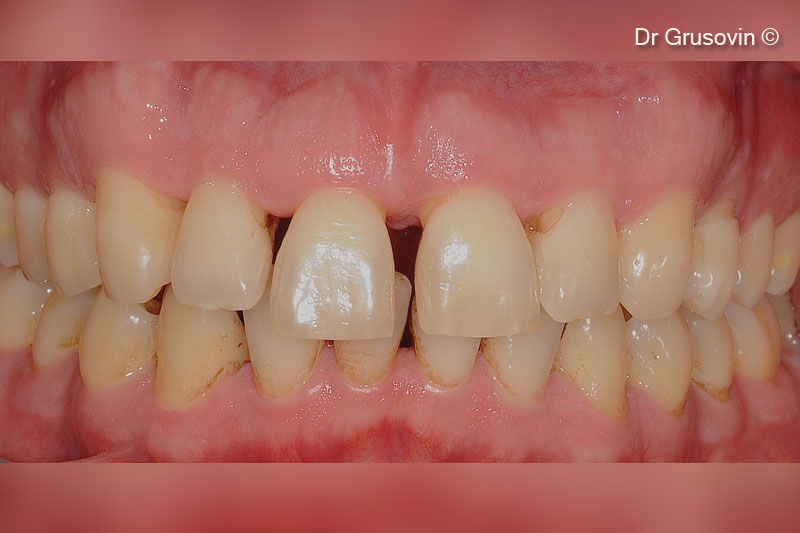

1. Healthy patient, non smoker intraoral clinical view buccal